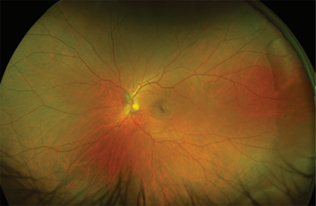

비문증 안저검사

연세비전안과에서 비문증의 원인을 파악하기위한 안저검사방법은 크게 두가지가 있습니다.

첫번째는 산동제를 점안하고 의사가 직접 검안경을 통해 확인하는 방법이고,

두번째는 초고해상도 무산동광각안저카메라를 이용하는 것입니다. 산동후 시행하는 안저검사는

산동될때까지 기다려야하기 때문에 약 30분정도 소요되나 정밀한 확인이 가능하다는 장점이 있으며,

무산동광각안저카메라를 통한 검사는 산동의 과정이 필요없이 약 5분만에 90%의 정확도로

신속한 검사가 가능하다는 장점이 있습니다.